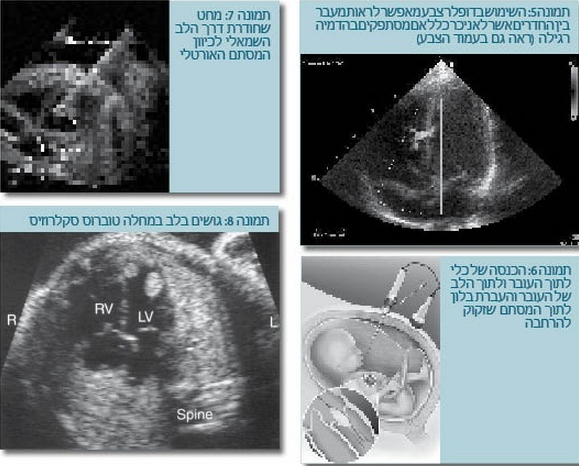

- מציאת גידולים בלב יכולה להביא לאבחון מחלה, כמו טרשת קרשית (Tuberous sclerosis), שיכולה להתבטא לעתים בתמונה נוירולוגית קשה מאוד עם פיגור שכלי והתכווצויות (תמונה 8).

יש מחקר מתקדם בטיפול תוך-רחמי במומי לב מסוימים, ובעתיד תהיה אולי אופציה לתקן בצורה זו חלק מהמומים. ייתכן שתהיה לכך חשיבות, למשל, במקרים של היצרות מסתמית אאורטלית קריטית בעובר. אנו יודעים שהיצרות כזו עלולה להביא לכך שהחדר השמאלי אינו גדל ומתפתחת במשך ההיריון - תמונה של תסמונת הלב השמאלי ההיפופלסטי. לפחות מבחינה תאורטית, הרחבה של המסתם בטרם החדר השמאלי הפך היפופלסטי תאפשר אולי גדילה של החדר השמאלי בעתיד (תמונה 6,7) ותיקון של שני חדרים לעומת תיקון על בסיס חדר אחד (ניתוח על שם פונטן, Fontan procedure), שהוא תיקון פחות טוב. הדבר נכון גם לגבי היצרות קריטית של המסתם הריאתי והיפופלזיה של החדר הימני.